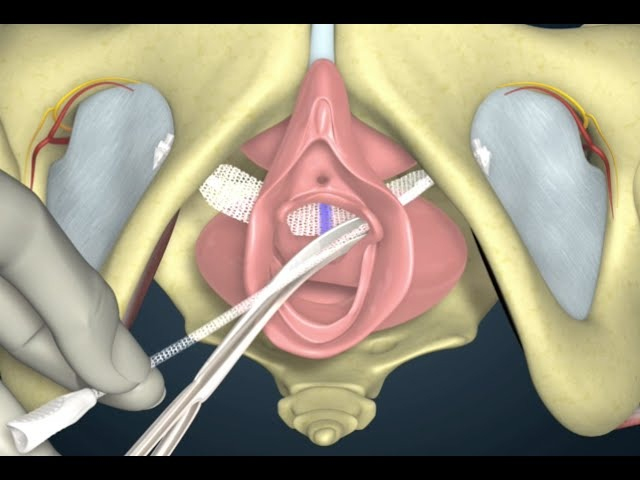

The TOT procedure is a minimally invasive surgical technique used to treat Stress Urinary Incontinence. It involves the placement of a synthetic mesh tape under the urethra to provide support and prevent involuntary urine leakage.